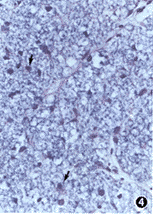

2.视神经少突胶质细胞:正常的视神经少突胶质细胞均匀分布于轴突周围。视神经间接损伤后14天时,有少突胶质细胞的增生,伤后30天时,少突胶质细胞增多达到较高水平(图4)。

图4 损伤30天,少突胶质细胞增生达较高水平(黑箭头) Luxol坚固蓝-HE×400